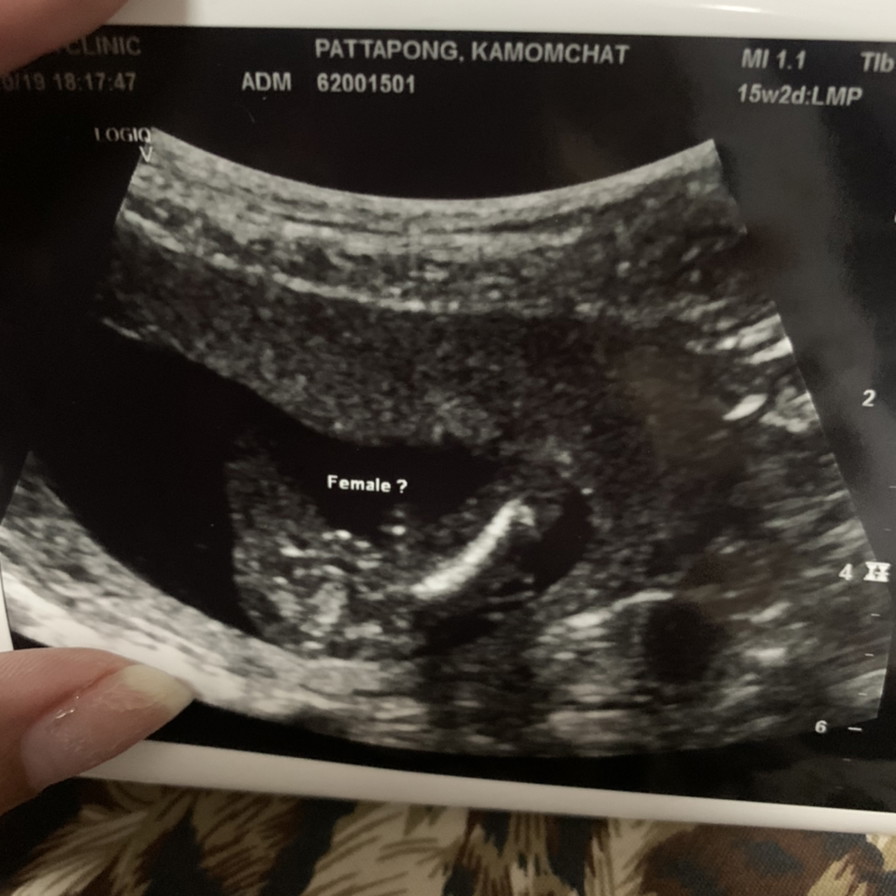

อยากรู้จังว่า ญ หรือ ช ???

1มี.ค63 ผ.ญค่ะ